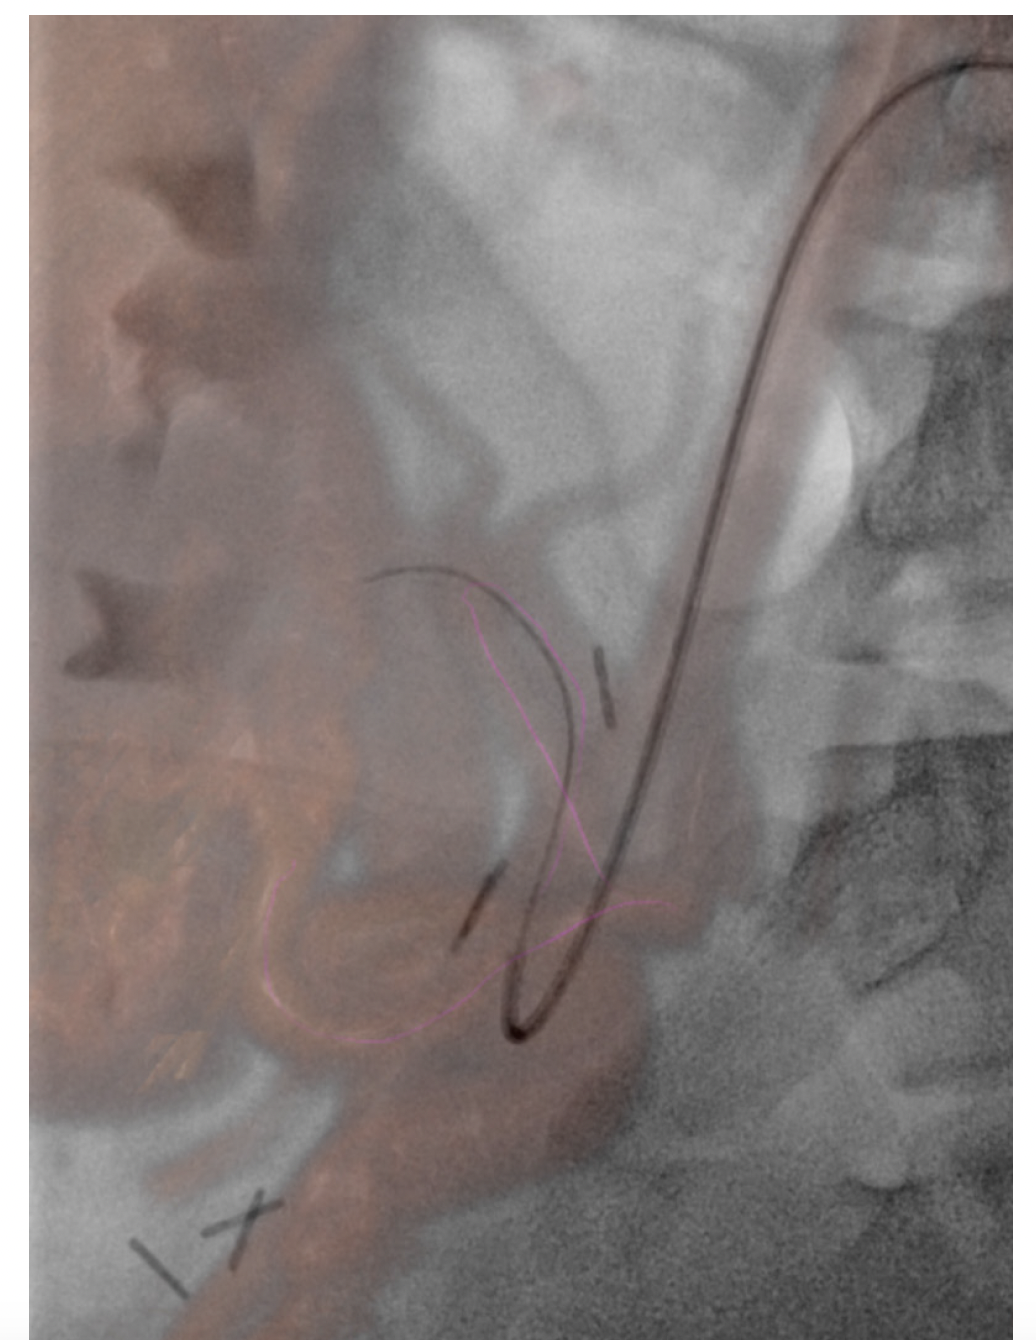

In pediatrics, MR and CT datasets are mainly used for fusion to assist with intraprocedural guidance and road mapping. As with most things in pediatrics, its use is currently limited. It is, however, an area of interest that is growing among the community. Sometimes patient vascular anatomy is complex; other times, patient size makes navigating even normal anatomy difficult. Though most interventionalists would be able to perform a complicated case without assistance, the datasets have potential to help decrease patient radiation and contrast dose in the hands of even the most skilled users. This may be able to be accomplished through use of the patient’s prior cross-sectional imaging to create 3D roadmaps on the day of treatment. While it may not be a “perfect” one-to-one recreation of the patient’s anatomy, the roadmap created and overlaid on live fluoroscopy is often more than sufficient (Figure 1). In complex cases, the roadmap created will at the very least give the interventionalist a better approximation of where a tortuous vessel’s origin might be in the 3D space (Figure 2). And if the interventionalist has a better idea of the vessel origin, they may be able to select it faster, thus limiting patient radiation and contrast dose. And while the same software can be used for even more advanced techniques such as organ segmenting, it is straightforward to use. It doesn’t matter how useful or “nifty” you think something is if it is unreliable and cumbersome to implement. Once the interventionalist understands Siemens’ simple and intuitive workflow, use of prior imaging in this manner is something that can easily be done with little effort and time. The other thing to keep in mind is with the simplified workflow; if whatever overlay was created using the patient’s prior imaging is not helpful or is a hinderance, it can easily be turned off. While it may seem counterintuitive, the ability to easily turn off an advanced feature if it is not serving its purpose is just as important as to not waste time in the suite doing unnecessary troubleshooting.

Navigational software is most useful in pediatric musculoskeletal interventions. If there is a small lesion in a difficult-to-get-to place and CT is either unavailable or unreliable, it is a wonderful tool. A safe needle trajectory can be preplanned off the original MR or CT. Once planned, it then can be fused to live fluoroscopy and the system will generate a virtual guide for the needle. By starting with a skin entry point then moving to a progression view, the needle can be safely guided down along the planned path to the area of interest. I place a high value on having a plan B or C if your original plan is not working. Siemens needle guidance software accomplishes just that. If the plan made from the patient’s original imaging is not working, the case can be easily troubleshot with syngo DynaCT. A syngo DynaCT can be performed, and a new trajectory can be planned so the case can continue. Troubleshooting with syngo DynaCT is made even easier with the new ARTIS icono. The technology allows for speedy acquisition at a reasonably low dose so if the original plan isn’t working, abandoning it and starting over with syngo DynaCT so that the case can safely be performed is a more palatable option.